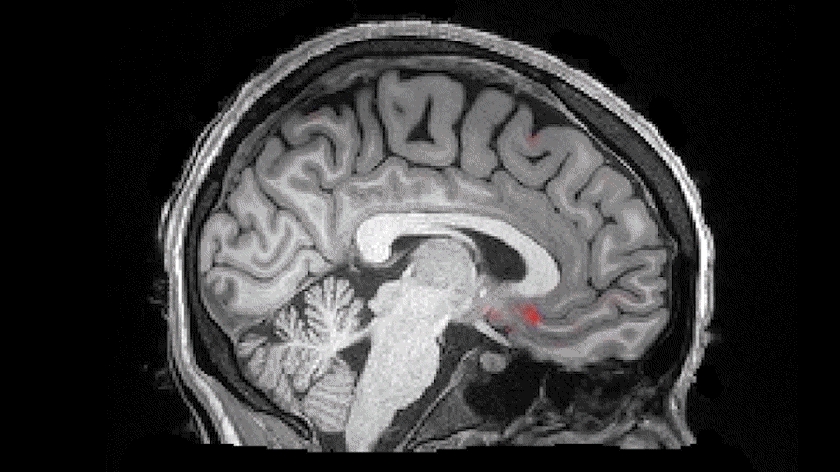

非快速动眼睡眠期间,血液(红色)从大脑流出后脑脊液(蓝色)流入脑室 | Laura Lewis, Boston University